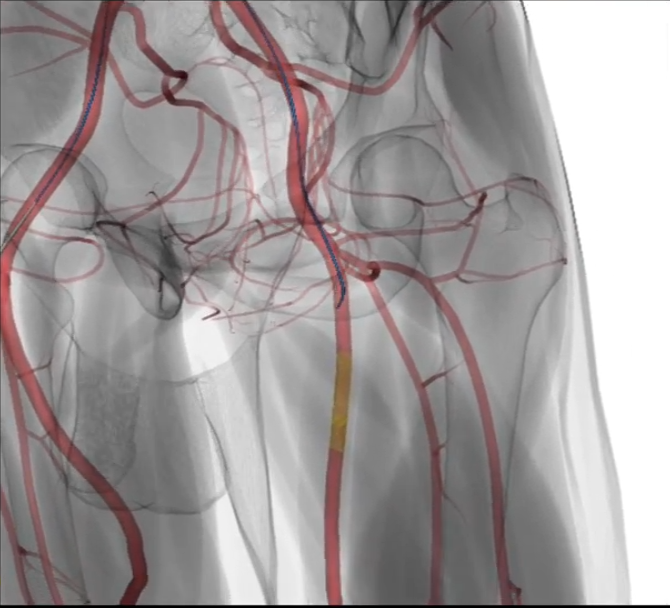

• Simultaneous X-ray and 3D visualization

• Improved spatial awareness

• Better understanding of disease patterns

• Accelerated learning experience